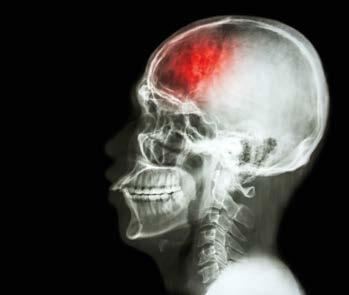

Erste Hilfe im Alter

Ein Schlaganfall stellt oft ein lebensveränderndes Ereignis dar und bedarf häufig einer langen und intensiven Rehabilitation.

Je f rüher ein Schlaganfall erkannt, die Rettungskette in Gang gesetzt wird und die oder der Betroffene medizinische Behandlung erhält, desto größer sind die Chancen, dieses Ereignis ohne bleibende Folgeschäden zu überstehen. Es gibt Schlaganfall-typische Symptome, die auch für Laien leicht erkennbar sind: Spricht eine Person plötzlich verwaschen oder kann einzelne Wörter nicht mehr aussprechen, kann dies ein Alarmsignal sein. Oft ist es nicht möglich, gleichförmig zu lächeln, auf der betroffenen Körperseite hängt der Mundwinkel nach unten. Schluckprobleme und Gedächtnislücken treten auf. Auch ist es typisch, dass eine Körperhälfte deutlich schwächer ist, so können Menschen auf der betroffenen Seite schwer die Hand zur Faust ballen oder ein Glas halten. Gangstörungen können auftreten. Besteht der Verdacht, dass es sich um einen Schlaganfall handelt, ist es wichtig, Ruhe zu bewahren und sofort die Rettung zu verständigen. Betroffene sind auf dem Boden am sichersten –sitzend mit erhöhtem Oberkörper oder bei Bewusstlosigkeit in stabiler Seitenlage. Wenn keine Vitalzeichen feststellbar sind, sind lebenserhaltende Maßnahmen bis zum Eintreffen der Rettung durchzuführen.

Nicht selten kommt es im Vorfeld eines Schlaganfalls zu oben genannten Symptomen, die sich oft spontan

innerhalb von mehreren Stunden oder wenigen Tagen wieder vollkommen zurückbilden. Hier wird von Betroffenen davon ausgegangen, dass alles wieder in Ordnung ist, und keine weitere medizinische Diagnostik veranlasst. Diese „Vorboten“ führen jedoch in vielen Fällen zu einem schwerwiegenderen Schlaganfall. Daher ist es wichtig, diese Vorboten ernst zu nehmen.

Um einem Schlaganfall vorzubeugen, sind ein gesunder Lebensstil, ausreichend Bewegung und regelmäßige ärztliche Kontrolluntersuchungen (Blutdruck, Blutfettwerte, Körpergewicht etc.) wichtig, damit einem gesunden, selbstbestimmten Altern nichts im Wege steht.